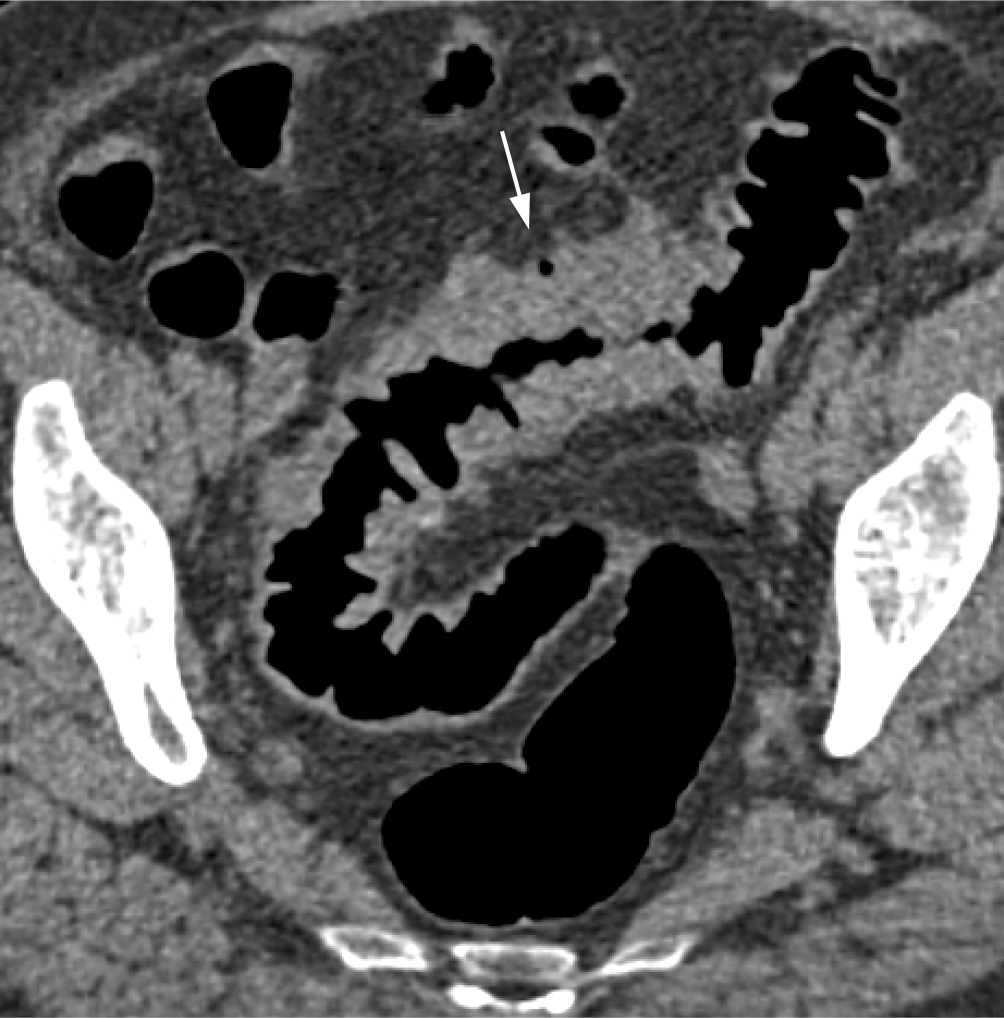

In einer Metaanalyse einer englischen Arbeitsgruppe hat sich gezeigt, dass die Rate an PICRC der CTK sehr gering und mit 4,4 % vergleichbar mit der der Koloskopie (2,9–8,6 %) ist [9]. Die retrospektive Aufarbeitung der übersehenen Karzinome in dieser Studie hat ergeben, dass 61 % retrospektiv sichtbar und somit Perzeptionsfehler ursächlich waren. Für die übrigen Fehlbefunde waren Fehler in der Untersuchungstechnik und beim PatientInnenmanagement verantwortlich (Abb. 8). Retrospektiv gar nicht abgrenzbare „okkulte“ Karzinome waren hingegen sehr selten. Fehldiagnosen können durch Optimierung der Untersuchungstechnik mittels spezifischem Training der Untersucher vermieden werden [38, 39].

Abb. 8

Fehldiagnosen eines kolorektalen Karzinoms (KRK) aufgrund technischer Fehler. a Fehlendes Fecal Tagging: Das zirkulär stenosierende Karzinom im Colon transversum ist innerhalb der nicht kontrastmittelmarkierten Flüssigkeit kaum erkennbar (Pfeil). b Anderer Patient mit Fecal Tagging: Das zirkulär stenosierende Karzinom im Colon descendens ist innerhalb der kontrastmittelmarkierten Flüssigkeit gut erkennbar (Pfeil). cd Unzureichende Sigmadistension in beiden Scanpositionen. Das stenosierende Karzinom im kollabierten Darmsegment ist leicht zu übersehen (Pfeil). e Koloskopisches Korrelat